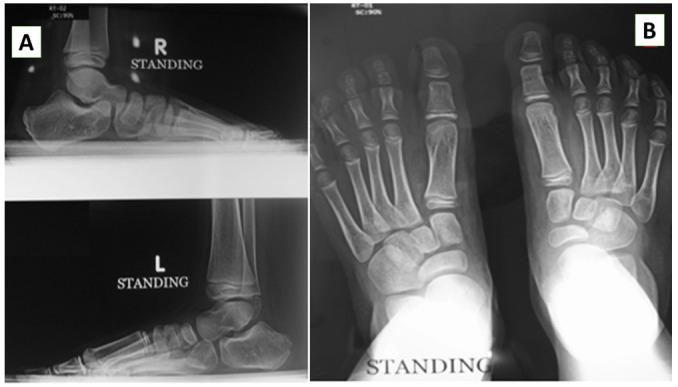

We conducted this prospective multicentre cohort study between August 2009 and November 2019. The included children were allocated into one of two groups according to the retention protocol. The Pirani and Laaveg-Ponseti scores were used to assess the feet clinically and functionally. Radiological assessment was performed using standing anteroposterior and lateral radiographs of the feet. We assessed the parents' satisfaction and adherence to the retention method. SPSS version 25 was used for the statistical analysis.

我们在2009年8月至2019年11月期间进行了这项前瞻性多中心队列研究。根据维持治疗方案,将纳入的儿童分为两组。使用皮拉尼和拉维格-庞塞蒂评分对足部进行临床和功能评估。通过站立位足部前后位和侧位X线片进行影像学评估。我们评估了家长对维持治疗方法的满意度和依从性。使用SPSS 25版进行统计分析。